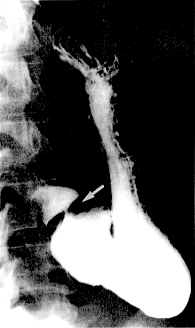

In fresh specimens a narrow (3.0mm to 4.0 mm) annular thickening, the pyloric ring, is felt in the wall of the gut at the gastro-duodenal junction. At laparotomy it may be difficult to palpate (Edwards and Rowlands l968), due to the effects of muscle relaxants administered during anaesthesia. On radiographs taken during the motor quiescent phase of the interdigestive myoelectric complex, the ring presents as a deep, clearcut, annular indentation separating the barium in the lumen of the stomach from that in the duodenum (Fig 11.1).

| Fig. 11.1. Radiograph of normal pyloric ring (arrow) in motor quiescent phase of interdigestive myoelectric complex |